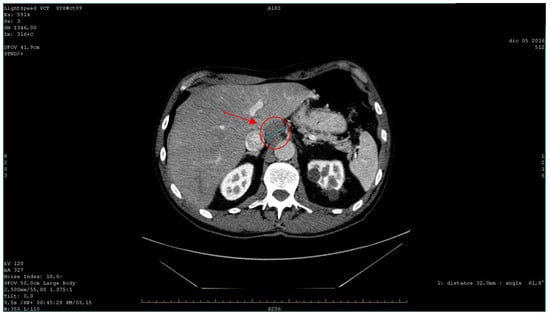

| 2016 | Patient presentation Diagnosis Abdominal ultrasound Total body CT scan  | Worsening non-productive night cough, no dyspnea. Metastatic lung cancer. Presence of malignant lymph nodes near the hepatic hilum. Solid nodular- like expansive process in the right upper lobe of the lung and multiple lymphadenopathies in the mediastinum and abdomen.  |

| 2016 | Partial response to therapy | Reduction in the size of the lung tumor and lymphadenopathies. |